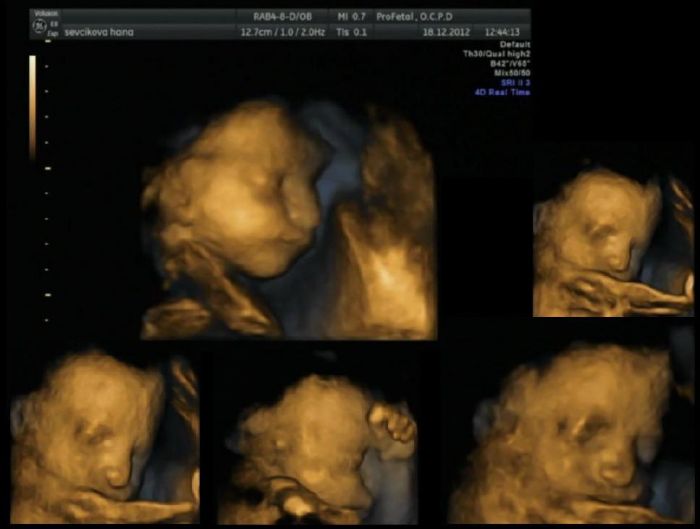

Jinak tady je moje koláž ze záběrů ze 3D ultrazvuku našeho Matěje

. Je hrozně podobný mému muži, jak jsem to viděla na tom ultrazvuku začala jsem se nezadržitelně smát, až mě doktor napomenul, že takhle z toho videa nic mít nebudu... a Mirek se smál taky, protože mu to bylo jasné. Miminko přece má být podobné na tatínka

Že jo, a Mirkovi se nelíbí (prý si počká až vyleze ven) ... tak jsem mu říkala, ať se podívá do zrcadla ten nos, tváře a rty (hlavně podle té největší fotky z 3D UZ) to je prostě Mirek když spí

. Ukazovala jsem to tchýni a ta taky říkala, že je to celý Mirek